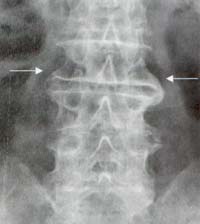

Osteofito marginal: corresponde a un sobrecrecimiento óseo que contiene hueso laminar y medular secundario a una herniación discal. A diferencia del sindesmofito marginal en los osteofitos la calcificación se origina del cuerpo vertebral y se dispone inicialmente en forma horizontal y más tardíamente en forma de gancho (Figura 3)

Figura 3. Radiografía frontal de columna lumbar Osteofitos a lo largo

de la columna lumbar, en forma de gancho (Flechas) que hacen puentes entre

un cuerpo vertebral y otro.